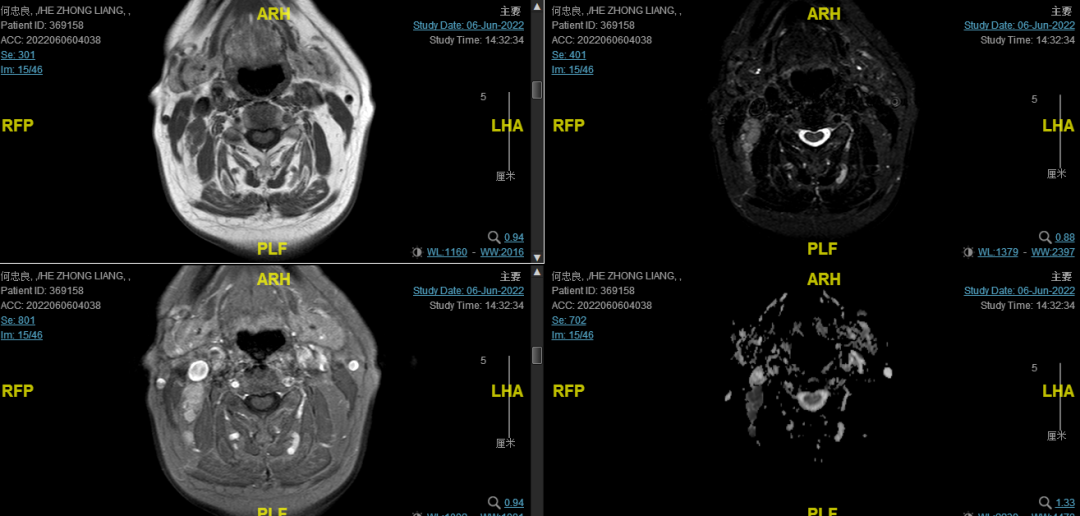

后患者至江苏省肿瘤医院放疗科就诊,2022-06-06完善头颅MR检查:

修正诊断:鼻咽癌T3N1M0,Ⅲ期。